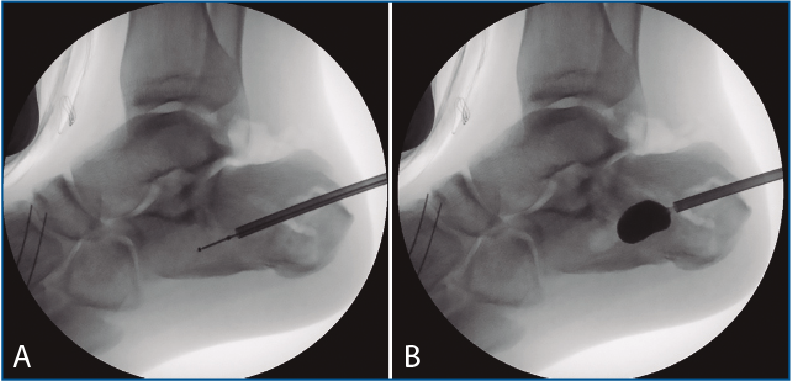

En los 2 casos restantes, tras la reducción controlada tanto con escopia como con artroscopia (Figuras 5A y 5B), se procedió a la inyección de hidroxiapatita, como describe la técnica de la calcaneoplastia.

Figura 5. A: control de escopia intraoperatoria (perfil) de la localización óptima para insuflar el balón de calcaneoplastia; B: control de escopia intraoperatoria (perfil) tras la insuflación del balón de calcaneoplastia.